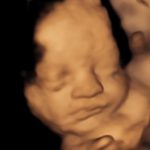

4D/5D/HD Ultrasound Gallery

Gallery